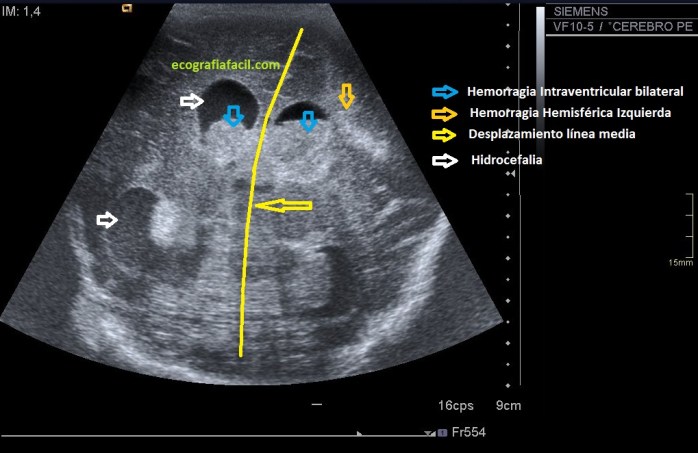

La patología más habitual y para la que se requiere la presencia del radiólogo en las unidades de cuidados intensivos neonatales es la hemorragia intracerebral:

• El riesgo de sufrir esta patología se da en pacientes con:

– Menos de 30 semanas de gestación.

– Pesos inferiores a 1500 grs.

• Existen 4 grados, siendo el más leve el 1 y el más grave el 4.

• Se objetivará la presencia hiperecogénica anormal en el parénquima cerebral debido a la presencia de sangre.

– El diagnóstico diferencial es la leucomalacia intraventricular que es el infarto y la necrosis de la sustancia blanca.

The most common pathology and for which the presence of the radiologist in the neonatal intensive care units is required is intracerebral hemorrhage:

• The risk of suffering this pathology occurs in patients with:

– Less than 30 weeks of gestation.

– Weights less than 1500 grs.

• There are 4 grades, the lightest being 1 and the most serious the 4.

• The abnormal hyperechogenic presence in the cerebral parenchyma will be objectified due to the presence of blood.

– The differential diagnosis is intraventricular leukomalacia, which is infarction and necrosis of the white matter.